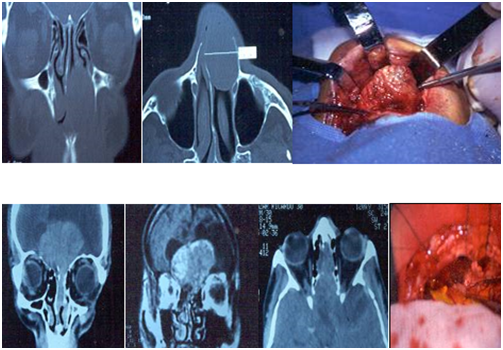

Two tumors were located at the supraclavicular fossa. The way of presentation of them was a tumor at the region of the neck. They were studied by tomography and MRI. The fine needle aspiratorion was non-especific. They were completely resected by a cervical approach. The possible nerves of origin were branches of the cervical sympathetic chain. There was no post operatory neurological deficit. There were no recurrences during the follow-up (5 years) (Figure 7).

Figure 7 Solitary neurofibroma (above), and neurilemoma (below), originated at branches of the cervical sympathetic chain. Complete resection.

Two patients had neurilemomas located at the nasal cavity. One of them, consulted for left nasal obstruction and another for epistaxis and bilateral disturbance of visual acuity.

They were evaluated by tomography and MRI. A neoplasm was located at the anterior area of the left nostril, and another had an endocranial origin, and had extension to the nasal cavity, eroding the lamina cribosa. In both cases, a biopsy was performed, and the diagnosis was schwannoma. The nerve of origin in both cases was the trigeminal. A neoplasm was completely resected by a sublabial approach, and in the other case, through a craneonasal approach. When performing the anterior craniotomy, it was found that the tumor was englobing the optical chiasm and the proximal area of both optic nerves, so a partial and conservative resection was performed. The patient with the nasal cavity neurilemoma had no neurological deficit.

The post operatory controls did not detect a recurrence during a 5-year follow-up in the case of the nasal tumor, and the patient with the intracranial neurilemoma with nasal extension had a better quality of life and improvement in visual acuity during the 2-year follow-up with residual tumor (Figure 8).

Figure 8 Neurilemoma originated at the trigeminal nerve.